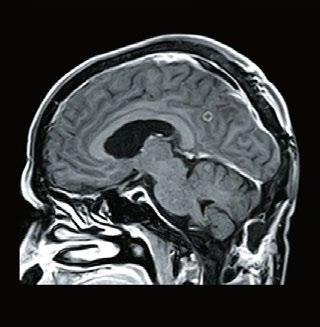

Figure 2, Axial MRIs of the brain. Left: T1-weighted image (short TE and TR). Right: T2-weighted image (long TE and TR). Figure 3, Olea Nova + software. Top row: MP2RAGE images from which the T1-map is calculated and FSE mEcho images used to calculate the T2-map. Bottom row: Two synthetic images with different imaging parameters.